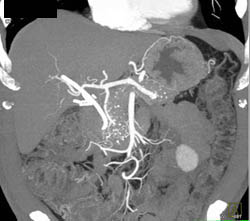

1 Cm Ampullary Mass